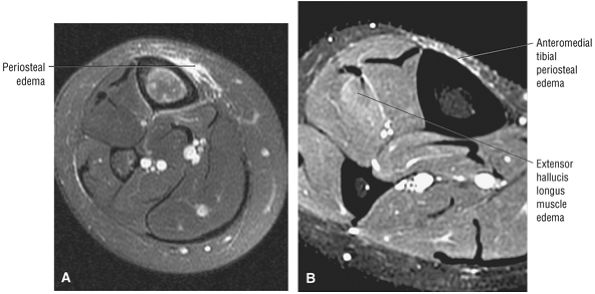

![]() |

|

FIGURE 5.58 ● transverse section through the midcalf shows the anterior and lateral compartments and their contents.